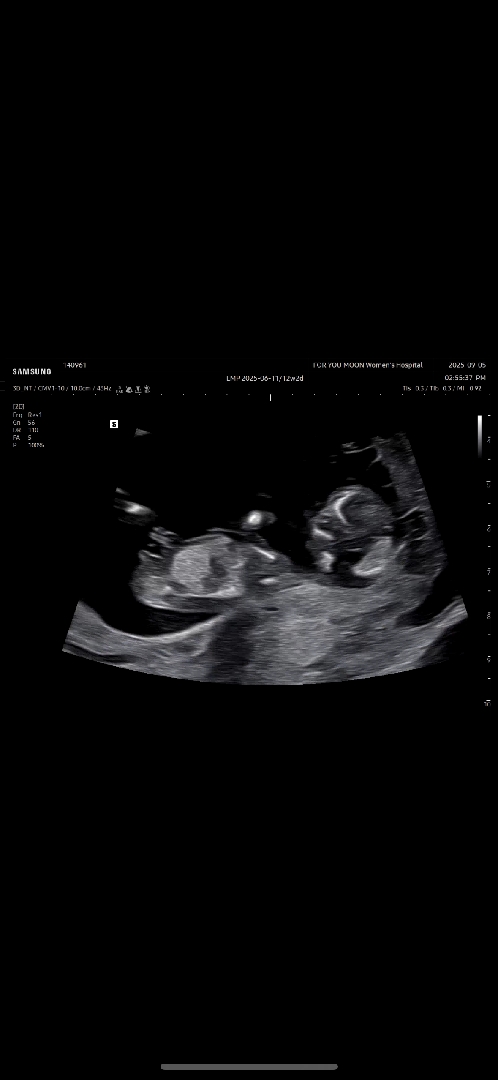

12주 각도법 봐주세요

아들같은데 고수님들 부탁드립니다

우아 아들각도닷